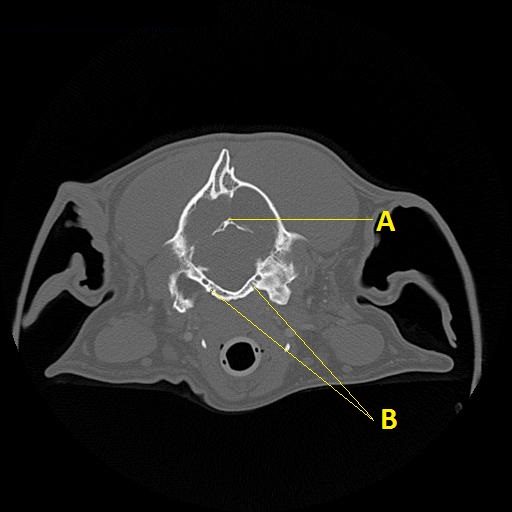

Q. Identify the structures labeled below:

A.

A. osteum tentorium cerebelli

B. hypoglossal canal